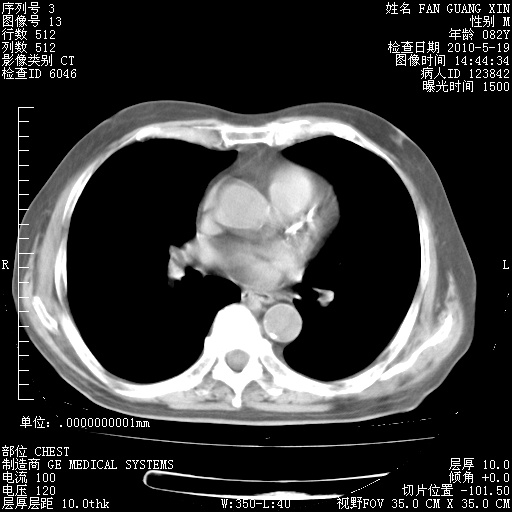

可改为口服强的松40-50mg/d治疗,若病情仍稳定,胸部阴影不再吸收可逐渐减量